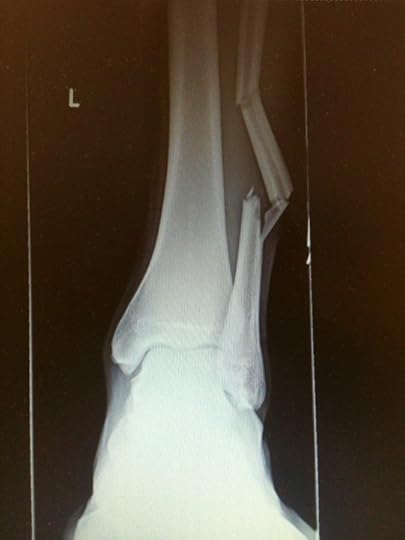

My son David broke his leg this week. Dashing across campus between classes, he hurdled over a retaining wall and heard the bone crack as he landed. He snapped it in two places and ended up having a rod surgically inserted to stabilize things just a few hours after the accident.

The surgeon told us it was a good thing we brought him in right away. At 6'7″, David is strong and muscular and his bones are extremely dense. The doctor had a hard time getting the rod in as it was — had the muscles been given time to swell, it would have made the job much more difficult, if not impossible.

Hebrews 4:12 tells us, "For the word of God is living and active and sharper than any two-edged sword, and piercing as far as the division of soul and spirit, of both joints and marrow, and able to judge the thoughts and intentions of the heart." Somehow, the idea of joints and marrow being split apart took on fresh meaning when I saw the X-ray of my son's splintered leg. The word of God brings conviction — how could I expect the process to be anything but painful? Whether we experience conviction of sin as as a sharp, shooting pang or a dull, aching throb, it won't go away until we climb onto the surgical table and let the Great Physician set things right.

David's break was not an open fracture, so the only external evidence was a slight bulge on the side of his leg. The true extent of his injury could only be appreciated by taking an X-ray to examine the bone inside. Likewise, God is far more concerned about our inner failings than our outward appearance. He searches our heart. That's why scriptures that speak to heart issues are always so piercing. The more I read, the more aware I become of how badly broken I am, and of how far I fall short of the goal, which is total conformity to Christ.